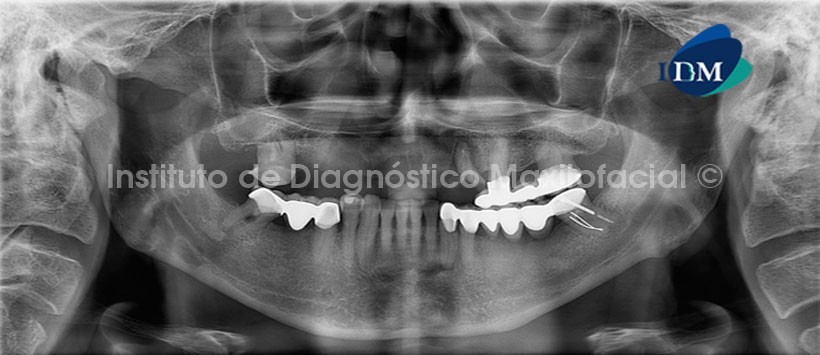

A la evaluacion con tomografía volumétrica, en la recontruccion panorámica del maxilar superior (Fig. 2), se evidencia la presencia de la fractura a nivel del tercio medio radicular en la pieza 2.3.